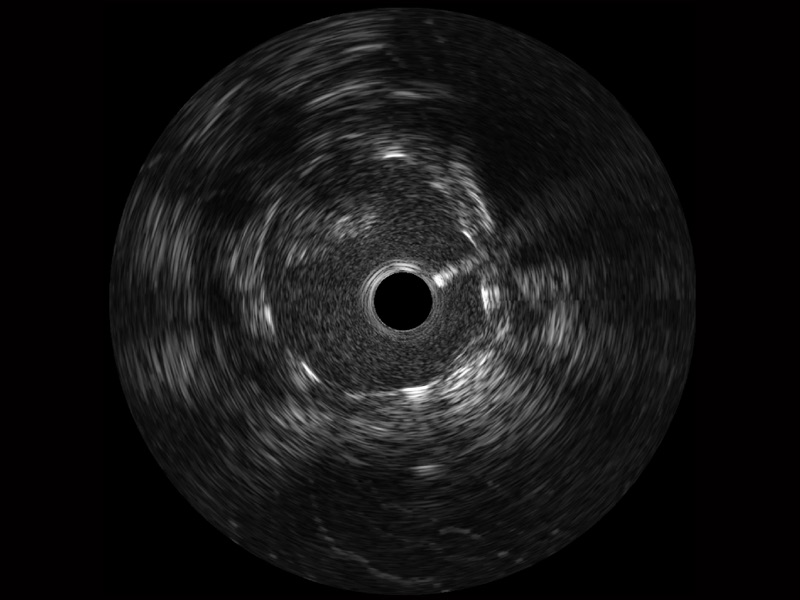

血管内超声(IVUS) 通过对病变程度、性质和累及范围的精确判断,可帮助选择治疗策略和方法,指导介入治疗过程,能够降低主要不良心血管事件,改善预后,在复杂病变介入治疗中用于指导支架置入的优势更为明显。血管内超声(IVUS)已成为精准心血管介入治疗的“金标准”。

乐玩lewin国际始终关注未满足的临床需求:超宽频成像技术同时提供高清分辨力和充足穿透深度,适应不同血管结构的治疗引导;智慧赋能,简化操作,降低临床应用难度和缩短学习曲线。